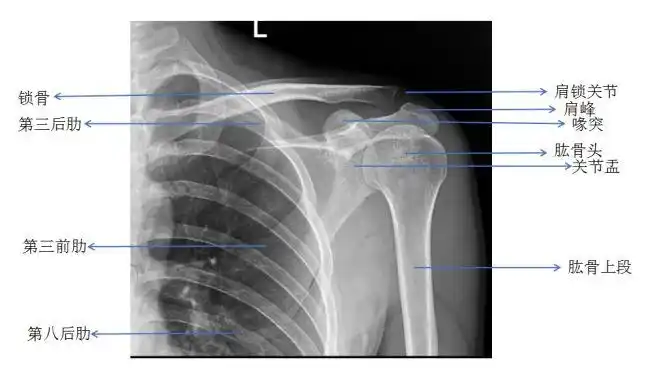

遇到肩部外伤时肩关节ct有必要做吗